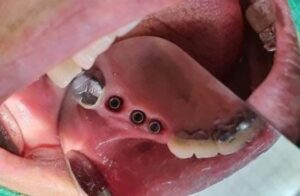

خبراء في العمل

يتم إجراء عمليات الزرع في مراكزنا من قبل فريق من أخصائي زراعة الأسنان ذوي المهارات العالية وأطباء الأسنان التجميليين للحصول على دقة جراحية متميزة وجماليات ممتازة للابتسامة

يترأس مراكزنا فريق مختار بعناية من خبراء زراعة الأسنان. وبعد عملية الزرع يتم تركيب التيجان والجسور ، والتي يتم تصميمها بأقصى قدر من الدقة والجمالية لمنحك الابتسامة المثالية.